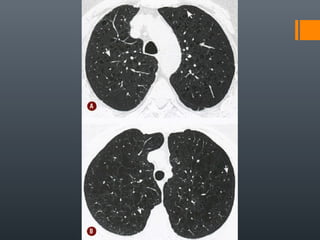

O documento discute vários conceitos radiológicos incluindo consolidação, atelectasia, nódulos, pseudocavidades e padrões intersticiais, fornecendo definições, sinais e diagnósticos diferenciais para cada tópico. Ele também discute a redução da atenuação pulmonar e fornece um link para mais informações.